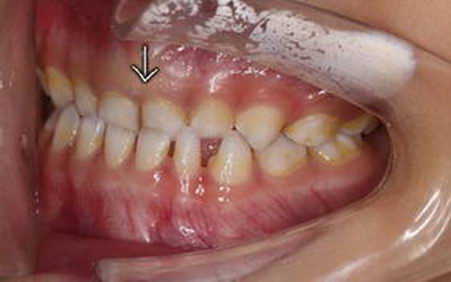

左图为4.5岁,右图为5岁,都是乳牙期间的地包天,即上面的门牙在下面门牙的内侧,会觉得孩子有一个明显的下颌前伸的动作,常伴随面中部的凹陷,容易下唇外翻,造成一定的面型发育问题。那么地包天是怎么形成的呢?

5岁男孩,通过4个月的早期矫正干预,

下唇外翻解决,脸型明显的改善。